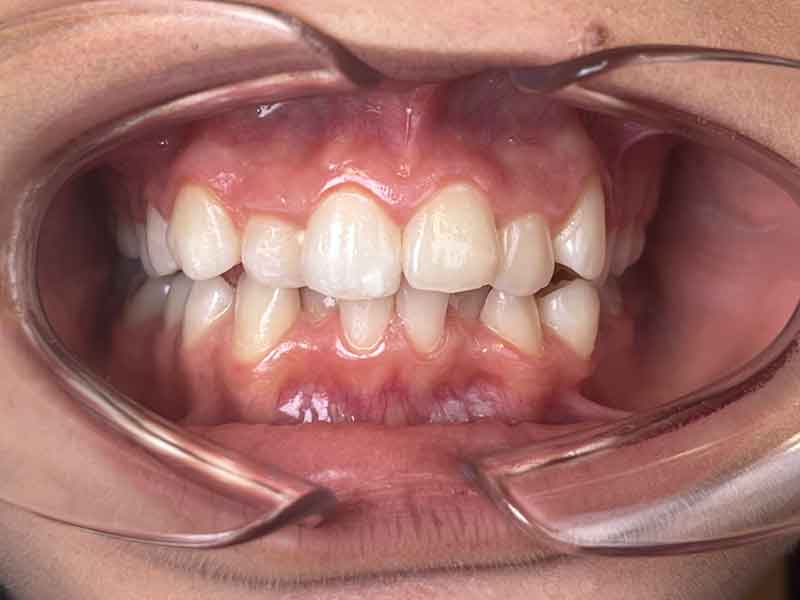

Situation initiale · Juin 2024

Quand les parents de cette jeune patiente de 13 ans consultent OrthoLight, la question n'est pas évidente à formuler : les dents ne semblent pas si mal alignées de face, mais quelque chose ne va pas. C'est en vue latérale que la situation apparaît clairement — et qu'elle justifie d'agir maintenant.

La vue latérale droite est très parlante. Le praticien observe deux problèmes liés :

Un décalage de Classe II

Les molaires et prémolaires supérieures sont en avance par rapport aux inférieures. Ce type de malocclusion traduit un déséquilibre dans la relation antéro-postérieure entre les deux mâchoires.

Une canine supérieure proéminente

Elle ne s'inscrit pas harmonieusement dans l'arcade. Ce signe révèle un manque de place transversal : le maxillaire n'a pas suffisamment grandi en largeur, créant à la fois cet encombrement et le décalage entre les arcades.

Les deux problèmes ont une cause commune : l'arcade supérieure est trop étroite. C'est sur elle que le traitement va agir directement.